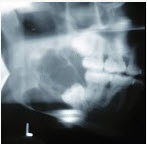

45、单项选择题

某患者一侧下颌磨牙区、下颌角及升支部渐进性膨大,按之有乒乓球感。X线片(如图)示多房性密度减低影,分房大小相差悬珠,分隔清晰锐利、阴影边缘呈切迹状,阴影内牙根尖有不规则吸收。该病最可能的诊断是()。

A.成釉细胞瘤